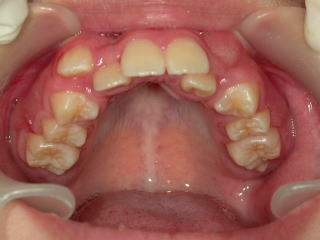

平成18年3月4日 初診 中学生女子です。(新潟県長岡市要町 要町歯科 歯科矯正 歯列矯正)